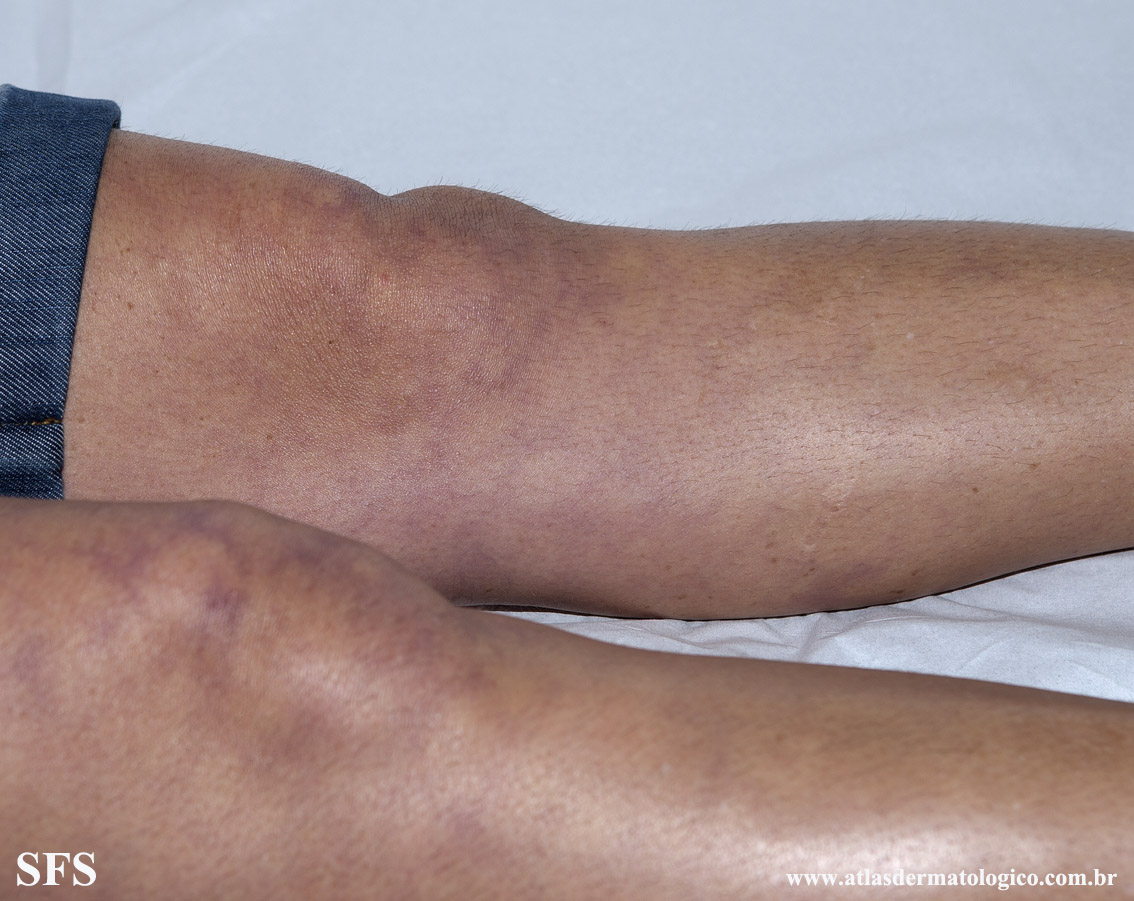

antiphospholipid antibody syndrome